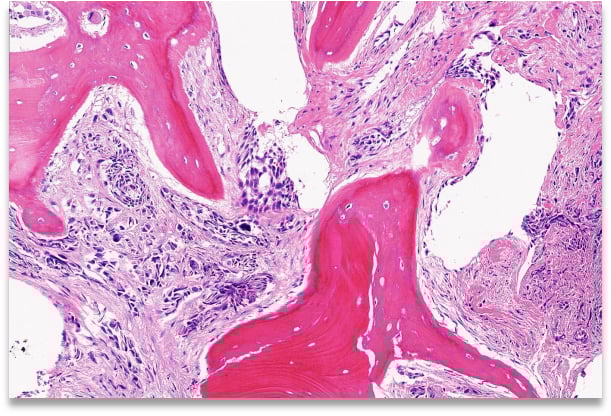

图1 患者切片HE染色图(部分截取)

在深入解读基因报告之前,我们必须先了解一个关键的技术前提:样本质量。对于发生骨转移的癌症患者,获取高质量的肿瘤组织样本用于二代测序(NGS)常常面临挑战。骨组织本身质地坚硬,在处理过程中通常需要“脱钙”步骤,而这一过程很可能成为基因检测的“拦路虎”。

许多临床指南和专家共识都强调了样本处理的重要性。例如,《骨肿瘤病理标本处理、取材和规范化病理报告临床实践指南(2023版)》中明确指出,如果使用浓硝酸、浓硫酸等强酸试剂进行脱钙,极大概率会导致核酸(DNA)降解,这样的样本送去做NGS检测,结果的准确性将大打折扣。因此,指南推荐使用温和的EDTA脱钙液,并且脱钙时间最好不超过48小时,以最大限度地保护核酸的完整性。